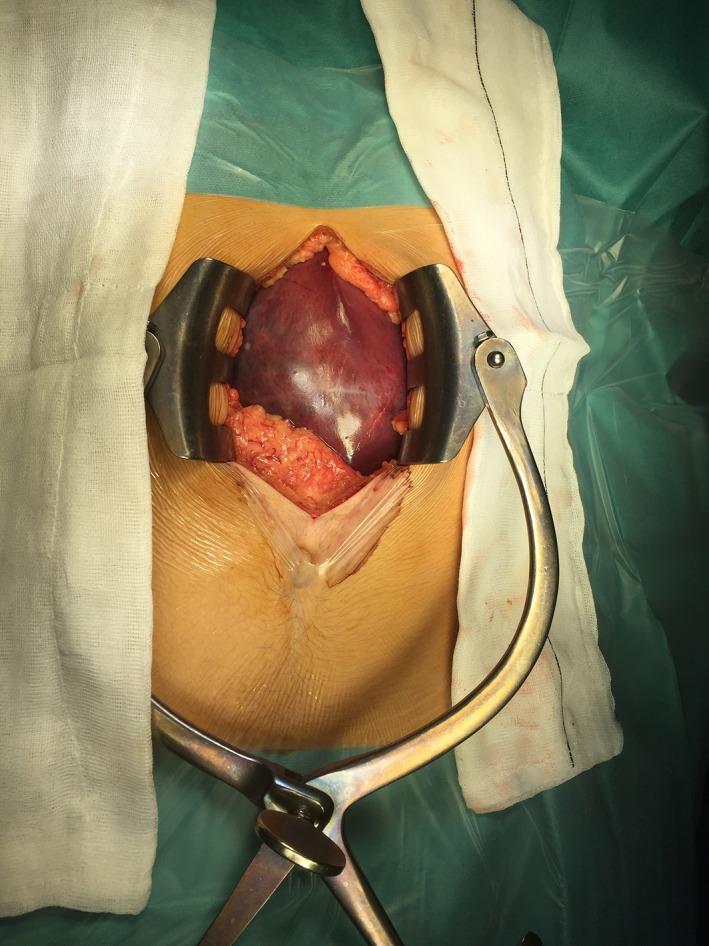

Partial splenectomy for a giant epidermoid cyst of the spleen.

The splenic epidermoid cysts are rare benign tumors, and a definitive treatment remains unclear. Although some spleen-preserving approaches have been reportedly used, splenic cyst recurrence usually occurs in true cyst cases, wherein the cyst is incompletely removed. In our case, partial splenectomy was performed and the giant cyst was completely removed.